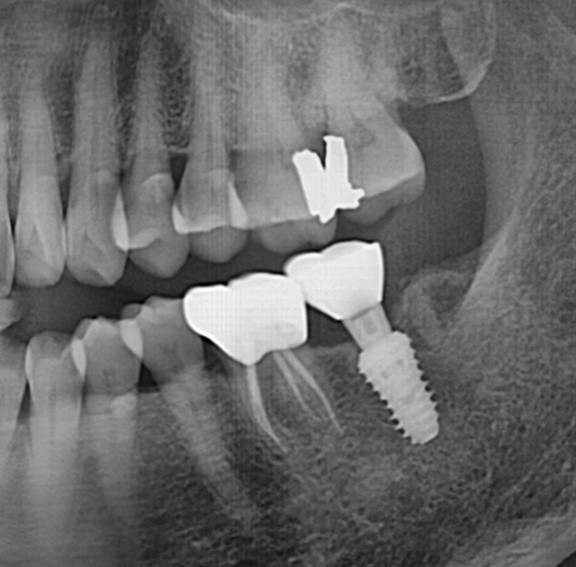

완전매복치사랑니 발치 + 구치부 임플란트 사례

전후사진

수술 전

수술 후